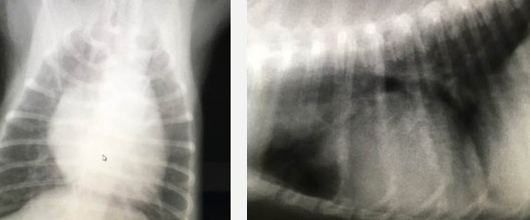

聴診、胸部レントゲン、心電図、胸部エコーなどにより、より高度な診察が可能となります。

心臓のサイズ・気管の位置・肺の状態 の検査を行います。